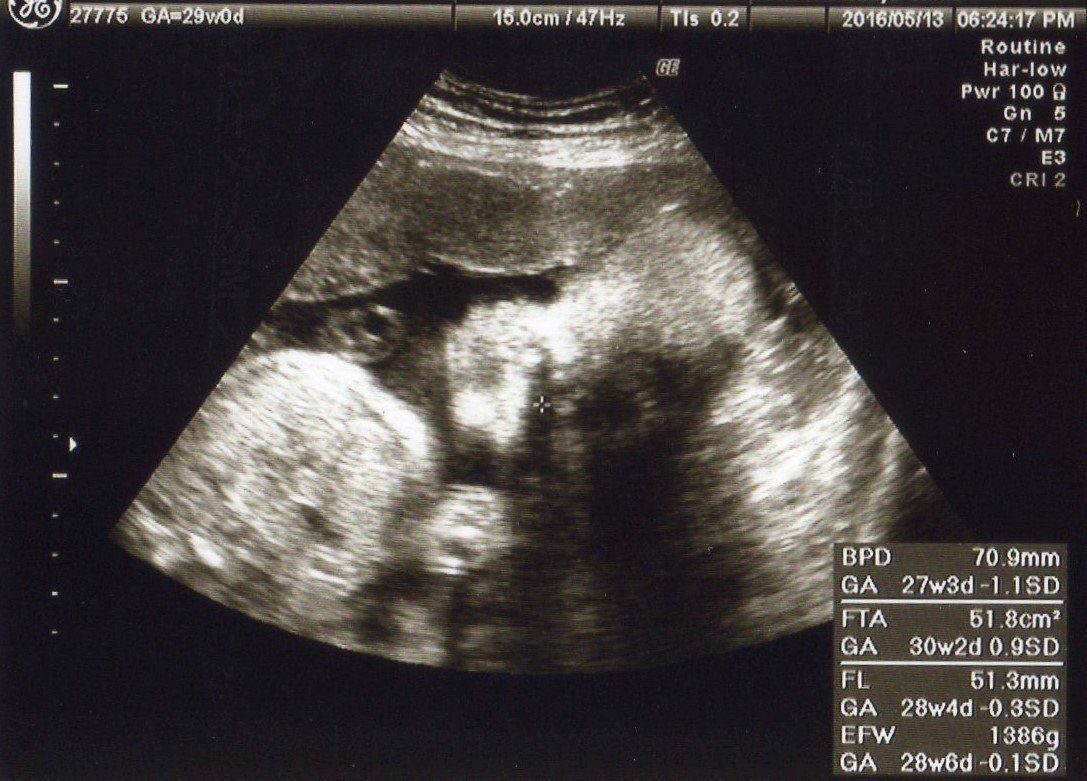

妊娠29週 推定体重が1000gを突破!

妊娠29週目の健診。赤ちゃんを真正面から見たエコー写真です。右上から斜めに頭・首・身体の順に見えます。EFW(胎児推定体重)がついに1000gを越えました!

胎動もだんだん活発になり、赤ちゃんの胎教に音楽を聴いたり、おなかを叩いて赤ちゃんと遊ぶ「キックゲーム」をしたり、いろいろと試しました。おなかにいる赤ちゃんとコミュニケーションがとれるなんて、不思議な気分でした。